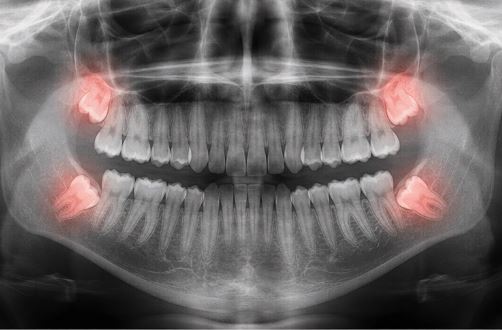

Диагностика перед удалением: рентген обязателен!

Перед удалением зуба мудрости обязательно делают рентгеновский снимок. Без него врач работает «вслепую», что опасно.

Минимум — прицельный снимок (визиограф): Видит зуб и ближайшие корни, но не всегда показывает, где проходит нижнечелюстной нерв.

Оптимум — КЛКТ (конусно-лучевая компьютерная томография) или панорамный снимок (ортопантомограмма): Показывает все зубы на челюсти, их положение, корни, близость к нижнечелюстному каналу (где проходит нерв), наличие кист, разрушение соседних зубов.

Особенно важна КТ при:

- Ретинированных «восьмерках» (не прорезались).

- Горизонтальном положении.

- Близости зуба к нерву (на снимке видно, есть ли риск повреждения нерва).

- Разрушение седьмого зуба из-за давления «восьмерки» (результат виден на рентгене).